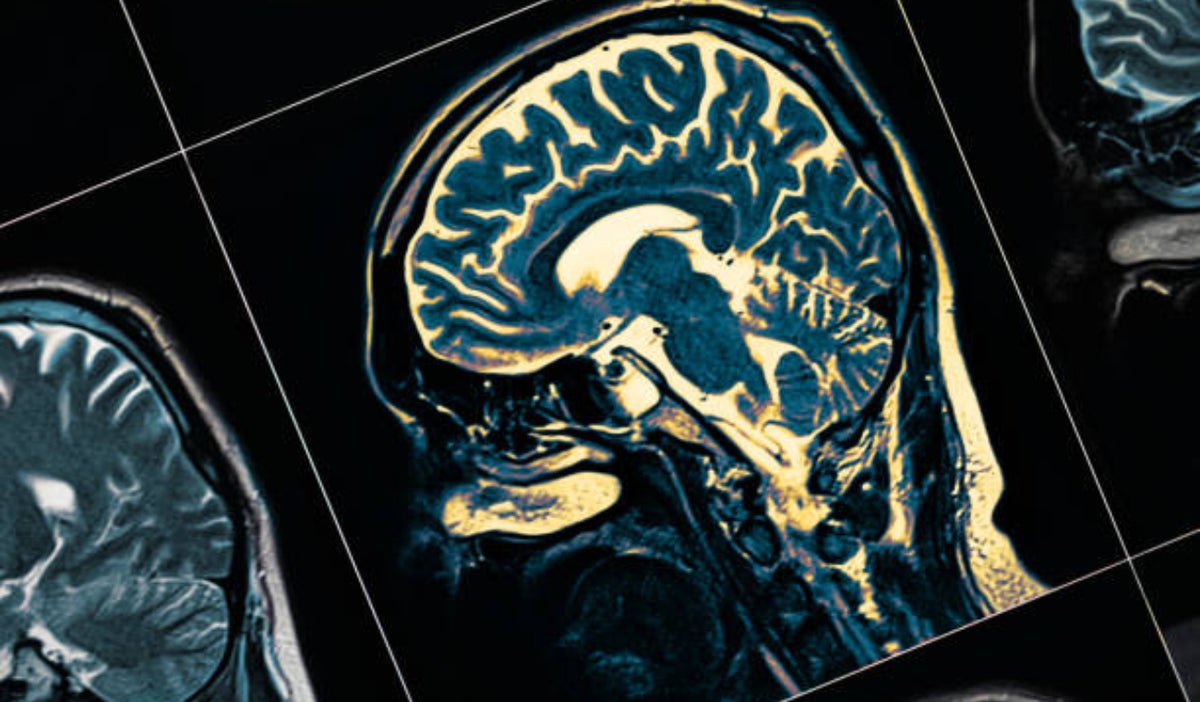

Hombre de 19 años es el paciente más joven con alzheimer a nivel mundial Crédito: iStock

El Alzheimer es un trastorno del cerebro que afecta gradualmente la memoria, el pensamiento y el comportamiento. Es un tipo de demencia que se caracteriza por el deterioro progresivo de las funciones cognitivas y la capacidad para llevar a cabo actividades diarias

Diagnóstico: Para diagnosticar el Alzheimer, los médicos realizan pruebas para evaluar el deterioro de la memoria y otras habilidades cognitivas. Estas pruebas pueden incluir evaluaciones neuropsicológicas, análisis de sangre y pruebas de imagen cerebral.